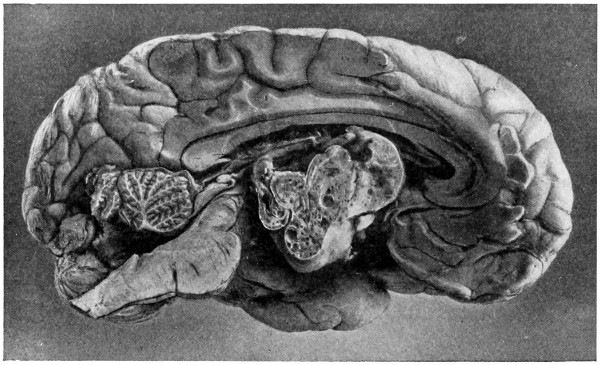

77. A cerebellar abscess 259

78. To illustrate diagrammatically the symptoms observed in cerebellar abscess formation (after Luciani) 261